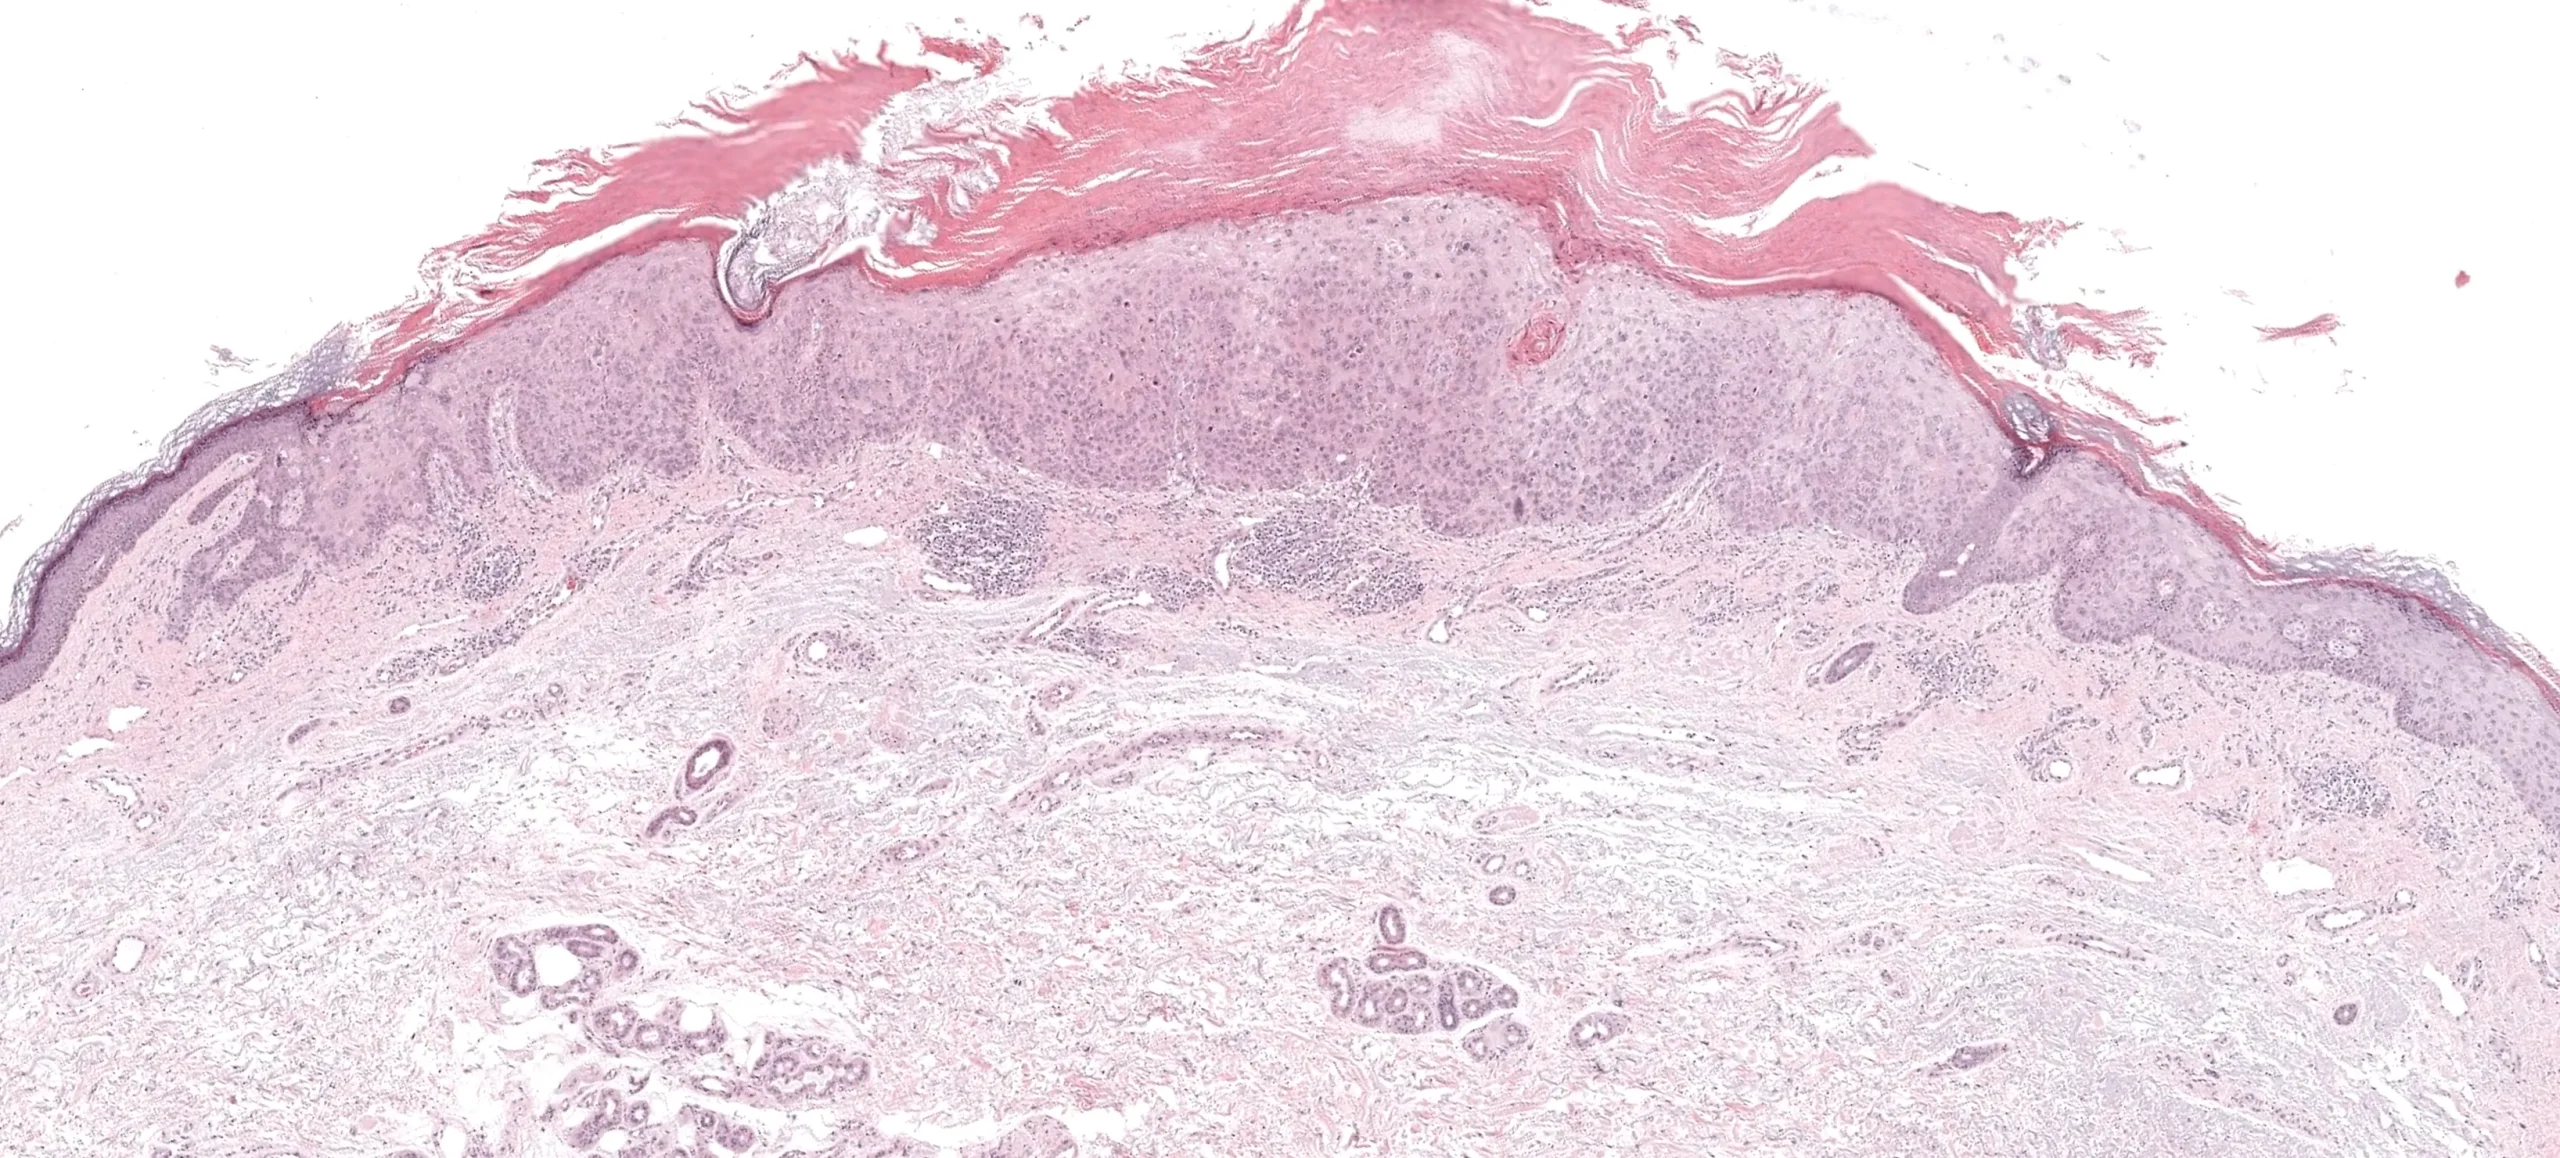

Dermatopatología diagnóstica

• Análisis histológico experto de biopsias de piel.

• Estudios de inmunohistoquímica e inmunofluorescencia.

• Enfoque en la correlación clínico patológica para diagnósticos más precisos.